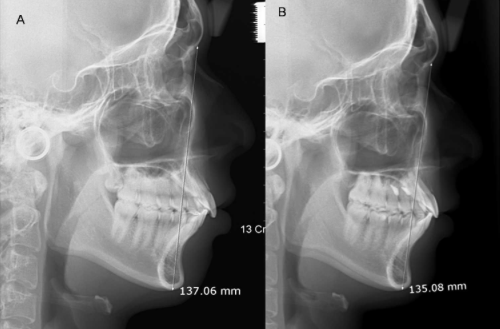

O estudo foi realizado em cefalogramas laterais e modelos digitais

adquiridos antes do tratamento (T1) e 10-12 semanas após a remoção do aparelho

fixo (T2). As medições cefalomérticas foram feitas usando o software Dolphin Imagining

11.0 (Dolphin Soluções de Imagem e Gestão, Chatsworth, Calif). E de modelo

foram feitas usando Orthomodel 2.0.206 Software (Orthomodel, Istambul,

Turquia). A relação molar foi avaliada em termos de diferença da ponta cúspide

mesio-vestibular do primeiro molar superior ao sulco mesio-lingual do primeiro

molar inferior.